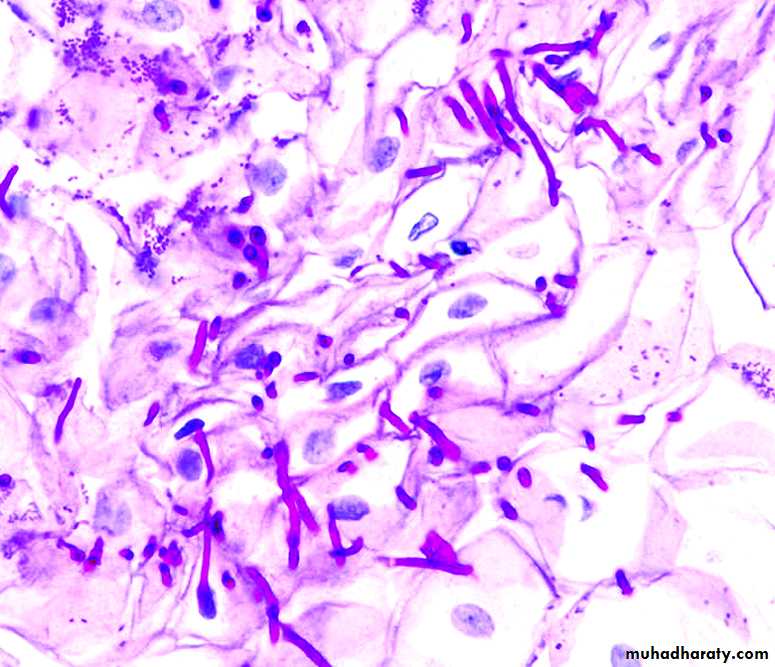

Oral Candidosis

Candida spp are fungi that have a wide distribution and that frequently form part of the commensal flora of the human body. Swabs taken from the skin, gut, vagina, or mouth of an apparently healthy individual all may show the presence of Candida species and, in particular, Candida albicans .Oral candidosis

Pseudomembranous candidiasis (oral thrush):

Characterized by white curd like pseudomembrane seen on the buccal mucosa, throat, tongue, or gingivaeRemoval of the membrane reveals an underlying erythematous mucosa